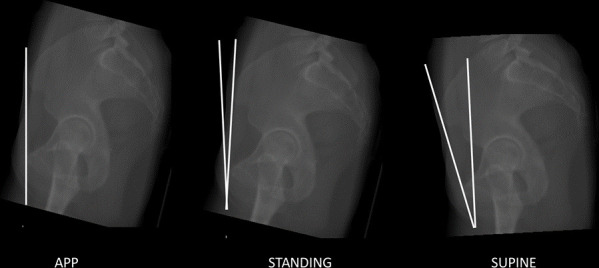

Methods: In total, 60 patients were selected from an institutional database: 20 with acetabular retroversion (AR), 20 with developmental dysplasia of the hip (DDH), and 20 with cam-type femoroacetabular impingement (FAI). Multiplanar CT reformats were created and the sagittal rotation was aligned to the APP. The sagittal pelvic orientation was then corrected until the anteroposterior (AP) projection mirrored that of their preoperative supine and standing plain radiographs. The change in sagittal pelvic tilt angle required was measured.

Results: The mean deviation from the APP in the AR group was 11.55° (SD 4.96°) for supine radiographs and 3.28° (SD 8.66°) for standing radiographs. The mean deviation from the APP in the DDH group was 12.2° (SD 4.26°) for supine radiographs and 6.96° (SD 3.43°) for standing radiographs. The main deviation from the APP in the FAI group was 8.63° (SD 5.21°) for supine radiographs and -1.28° (SD 7.31°) for standing.